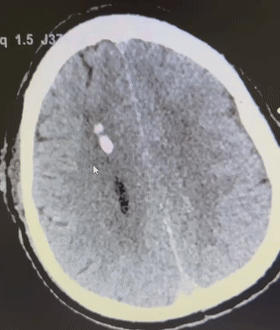

据了解,这名71岁高龄的老伯,因高血压小脑出血被急诊收治入住中南大学湘雅二医院桂林医院神经外科监护病区。当天7时左右,老伯突然出现意识障碍加深、神志昏迷的症状,且GCS(格拉斯哥昏迷指数评分,是一种评估昏迷患者的诊断指标,满分15分)评分仅为7分。急诊医生立刻复查患者头部CT,结果提示患者小脑出血且水肿加重、四脑室受压变形、幕上梗阻性脑积水并脑疝危象。

术前CT